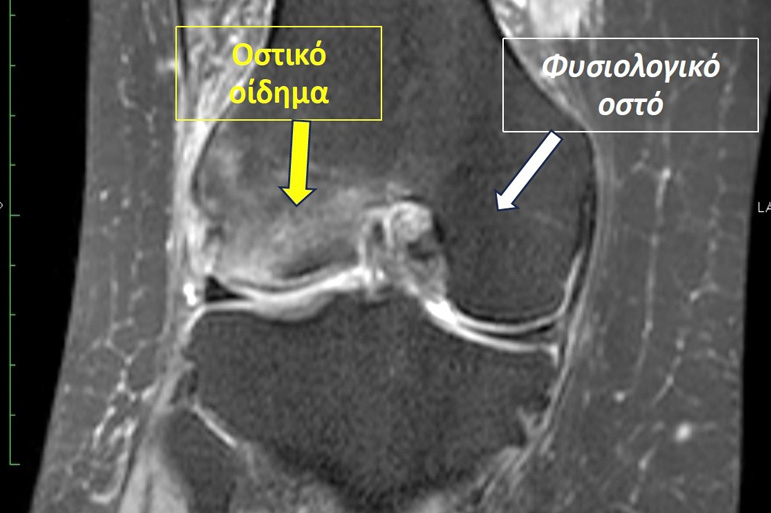

Τα οστά, εξωτερικά έχουν ένα σκληρό περίβλημα (φλοιός), ενώ εσωτερικά έχουν σπογγώδη μορφή και αποτελούνται από δοκίδες. Ως οστικό οίδημα ορίζεται η οστική βλάβη κατά την οποία «εξέρχεται» υγρό από τα τριχοειδή αγγεία των οστών στο διάμεσο χώρο των δοκίδων τους. Συμβαίνει δηλαδή ότι ακριβώς συμβαίνει και με το οίδημα σε οποιοδήποτε άλλο ιστό. Στους μαλακούς ιστούς όμως, όπως ξέρουμε, το οίδημα σημαίνει διόγκωση («πρήξιμο»), κάτι που φυσικά δε συμβαίνει στα οστά που έχουν στερεή και ανένδοτη δομή. Η καταγραφή του οστικού οιδήματος γίνεται μόνο με την μαγνητική τομογραφία. Όταν εμφανίζεται οστικό οίδημα μετά από μία κάκωση τότε πιθανολογούμε ότι ίσως κάποιες από τις δοκίδες του σπογγώδους οστού έχουν υποστεί ρήξη – μικροκάταγμα. Αν και μπορεί να εμφανιστεί σε οποιοδήποτε από τα οστά του σώματος, εμφανίζεται συχνότερα στα οστά των κάτω άκρων. Ειδικότερα, προσβάλλει συνήθως στα οστά που δέχονται μεγάλα φορτία όπως συμβαίνει στις αρθρώσεις των ισχίων, των γονάτων και των ποδοκνημικών («αστράγαλοι»).

Η κατάλληλη διαγνωστική εξέταση για τον εντοπισμό του είναι η μαγνητική τομογραφία. Πριν την εμφάνισή της, τα οστικά οιδήματα δεν μπορούσαν να αναγνωριστούν μέσω των συμβατικών ακτινογραφιών, με αποτέλεσμα λανθασμένες διαγνώσεις και αποτυχημένες θεραπείες. Επίσης, μπορεί να απαιτηθεί και η διενέργεια αιματολογικών εξετάσεων για τον αποκλεισμό λοιμώξεων ή αυτοάνοσων νοσημάτων.